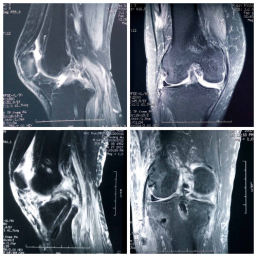

近日,我院运动创伤与关节镜外科成功治疗一例陈旧性膝关节脱位复合后交叉韧带断裂及后外侧复合体断裂患者,自体移植肌腱重建后交叉韧带及后外侧复合体。病人目前已顺利出院。

患者,男性,65岁,因车祸伤致右膝膝关节不稳及活动受限7月余收住我院运动创伤与关节镜外科。患者7月前因车祸伤导致全身多发伤:颅脑损伤、胸腰椎多节段损伤、多处肋骨骨折、左下肢胫骨骨折外院多次手术治疗。后因右膝关节严重不稳就诊于我科徐洪港副主任医师,患者就诊时右膝关节严重失稳定,静息状态下右膝关节可诱发多向不稳定及脱位,患者极度痛苦,受伤后患者长期卧床无法自行行走。因患者高龄并且损伤严重,曾多次就诊我省及外省多家三甲医院,因患者伤情较重,均未收住。患者入院后科室多次组织专家讨论,考虑患者目前陈旧性损伤伤情严重、右膝关节多组韧带损伤,并且因长期废用导致右下肢骨质条件极差又极大的增加了患者的治疗难度。我科徐洪港副主任医师术前结合患者病史、体检及必要的影像学检查,制定了详细的手术方案及预案,术中采用自体移植肌腱关节镜下解剖重建后交叉韧带同期微创有限切口自体肌腱移植重建后外侧复合体(LaPrade技术)。手术顺利,术中术后患者无输血,术后第二天即可扶拐杖下地活动,迅速恢复生活能力。